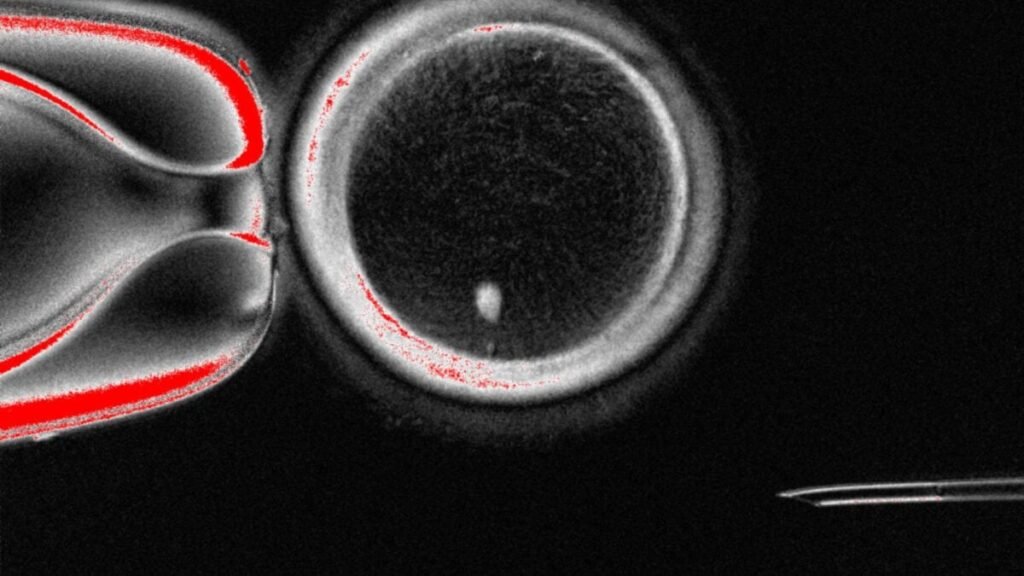

To create these eggs, the researchers replaced the nucleus of an egg cell with that of a skin cell—a method called somatic cell nuclear transfer. The method had previously been used to create cloned animals, such as Dolly the sheep.

They generated 82 functional eggs in total. Of these, 9% were successfully fertilized by sperm and developed into a blastocyst, the ball of cells that forms from a zygote about five days into fertilization. Researchers typically only study embryos in the lab until they reach the blastocyst stage, which is also when doctors usually implant an embryo created through IVF in someone’s uterus.